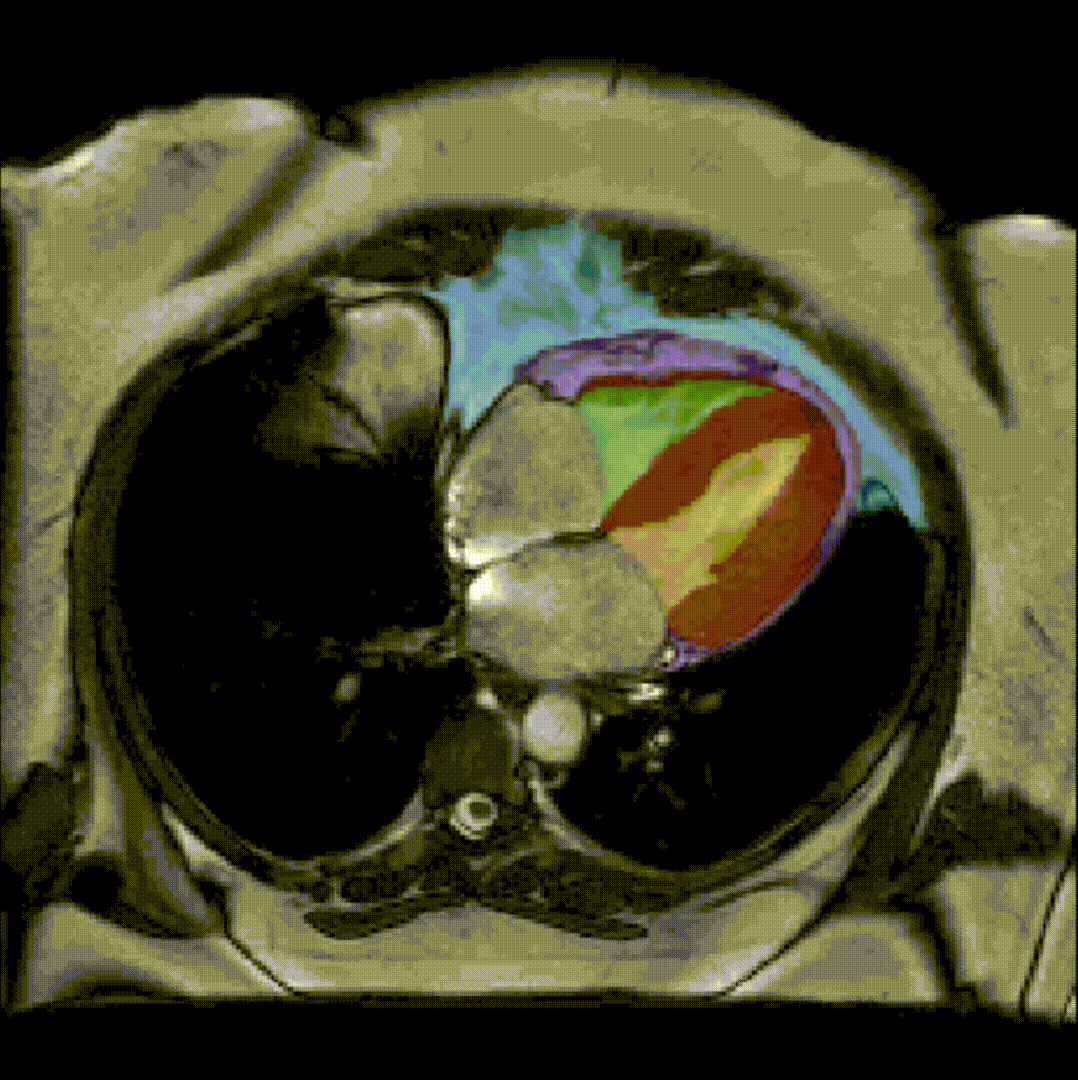

Semi-automatic segmentation of epicardial muscle and fat tissue on a cardiac cine MRI sequence.